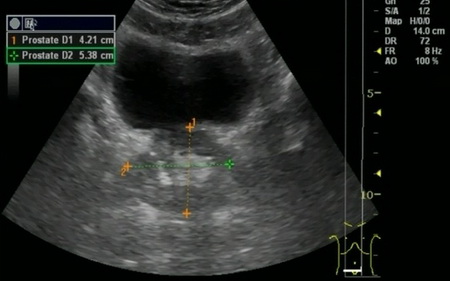

Рис. №1. УЗИ мочевого пузыря и предстательной железы. Объем предстательной железы 52 см3.